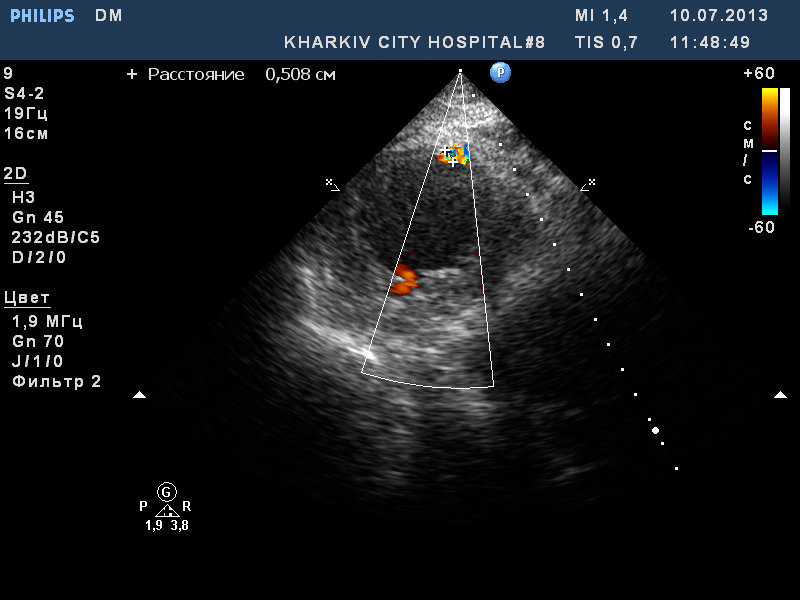

Постинфарктная аневризма с разрывом МЖП

Пациент 73 лет с острым инфарктом миокарда. При осмотре дискинезия верхушки (аневризма).

Визуализируется шунт в верхушечном сегменте МЖП (сброс слева-направо до 0.6см по ширине потока).